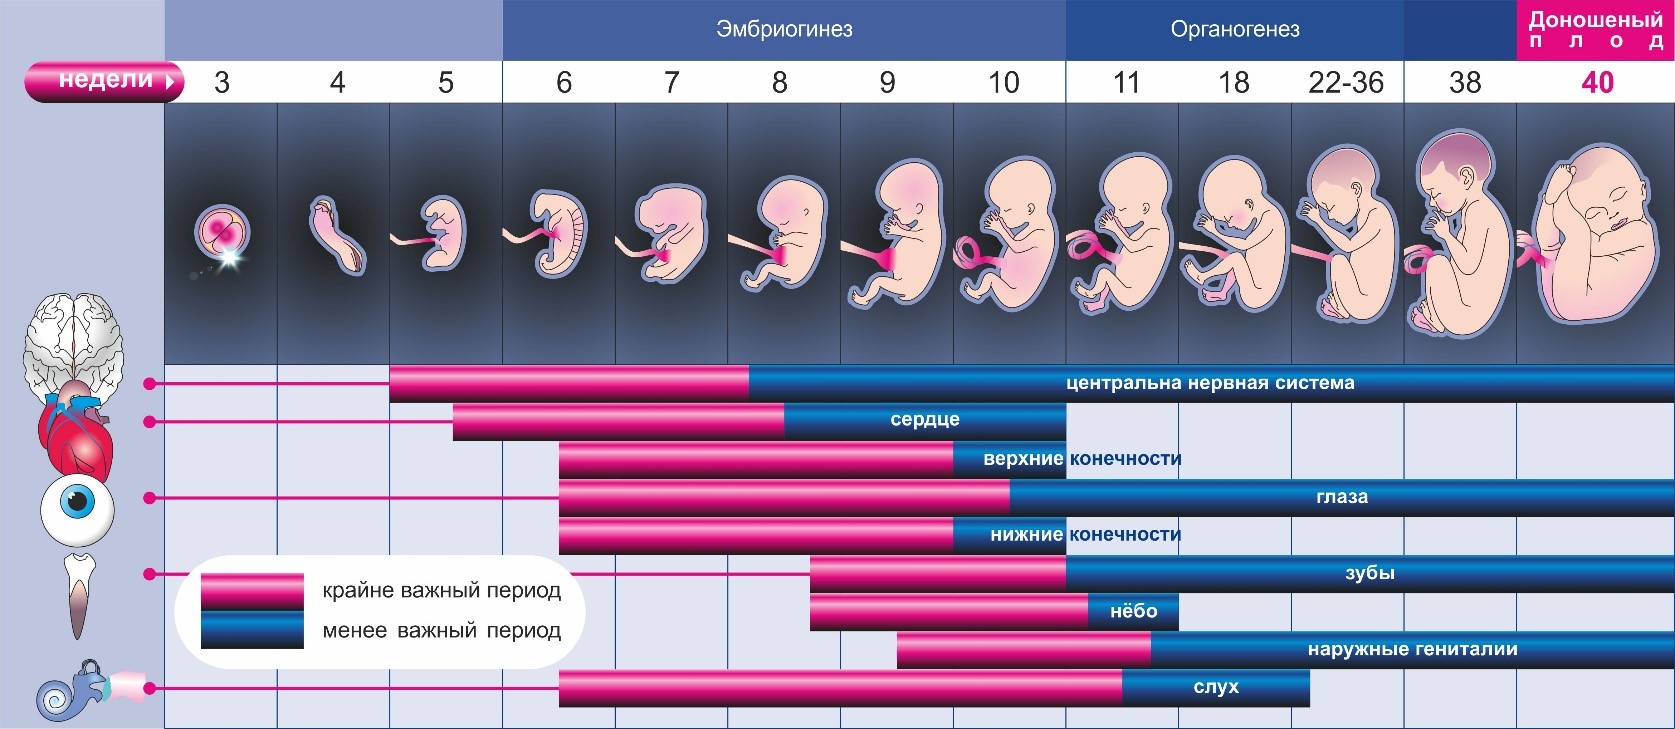

Первые три месяца – это очень важное время и для вас, и для малыша. Он проходит массу преобразований, за считанные дни меняется полностью, закладывается основа всех его органов и систем

Он проходит массу преобразований, за считанные дни меняется полностью, закладывается основа всех его органов и систем. После трех месяцев он начинает вас отчетливо чувствовать, даже реагировать на ваше настроение, звуки, прикосновения – движением.